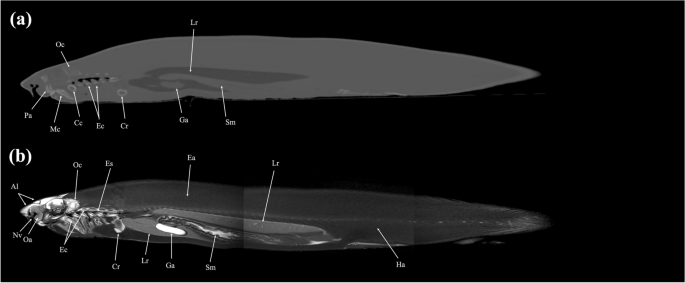

Sagittal (a) CT and (b) MR images of a banded houndshark (Triakis scyllium) at level 15 of Fig. 25. Al Ampullae of Lorenzini, Cc Ceratohyal cartilage, Cr Coracoid bar, Ec Epibranchial and ceratobranchial cartilage, Es Esophagus, Ga Gall bladder, Mc Meckel’s cartilage, Oa Olfactory lamellae, Oc Otic capsule, Pa Palatoquadrate, Sm Stomach, Nv Nasal cavity.

Mid-sagittal (a) CT and (b) MR images of a banded houndshark (Triakis scyllium) at level 16 of Fig. 25. Al Ampullae of Lorenzini, At Atrium, Ba Basihyal cartilage, Cb Cerebrum, Ce Cerebellum, Cl cloaca, Co Coracomandibularis, Cr Coracoid bar, Ch Coracohyoideus, Ct Ceratotrichia, Da Dorsal aorta, Ea Epaxial, Es Esophagus, Ga Gall bladder, Ha Hypaxial, Ic Internasal cartilage, Kd Kidney, Lr Liver, Me Medulla oblongata, Ne Neurocranium, Nu Neural arch, Oa Olfactory lamellae, Ol Optic lobe, Rc Radial cartilage, Sc Spinal cord, Te Teeth, Ts Transverse septum, Vi Valvular intestine, Ve Ventricle, Vt Ventral constrictors, Vc Vertebral centrum, Sm Stomach, Sv Spiral valve.